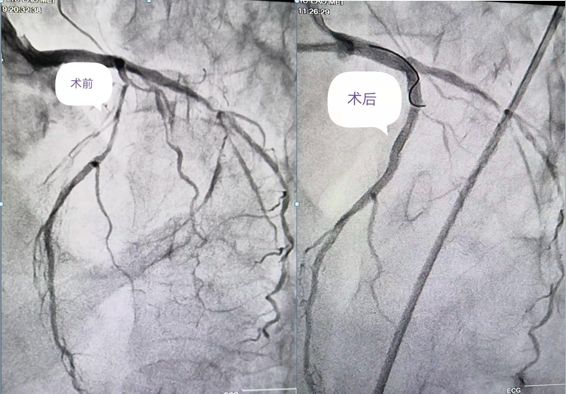

刘大娘今年70岁,家住秀山县。因“上腹疼痛1月余,腹胀纳差6天”到重医大附二院秀山分院消化内科住院,伴有糖尿病、高血压病史多年。入院后查心电图及肌钙蛋白异常,经过心内科医生会诊后考虑为急性非ST段抬高型心肌梗死,立即转入心内科治疗,紧急行冠脉造影提示冠脉三支病变:前降支近段至中段弥漫性病变伴严重钙化,狭窄最重达90%;回旋支中远段弥漫性病变,狭窄最重达85%;右冠最重病变狭窄程度达95%。

由于病情十分危重,经过规范的冠心病药物治疗,胸痛症状仍没有明显好转;病变处钙化非常严重,于前降支病变处行球囊扩张时,球囊无法扩张。就在刘大娘及家属处于绝望边际之时,在秀山分院挂职副院长的重医大附二院心血管内科陈运清教授了解情况后,多次组织心内科医生讨论病情、制定治疗方案,并反复与大娘及家属沟通,最后终于打消顾虑,一致决定择期行血管内超声指导下(IVUS)的冠脉旋磨术和冠脉介入治疗。

没有金刚钻,不揽瓷器活。”7月19日,手术由陈运清教授主刀,首先进行了IVUS检查,提示冠脉病变呈360°钙化;随后,对病变处成功进行了冠脉内旋磨术和支架植入术,并用IVUS复查证实支架覆盖全部病变且贴壁良好,完成血运重建。术后,大娘病情好转,疼痛症状明显消失。26日,阳光普照,当陈教授来到心血管内科A区5号病床时,刘大娘和家人们正在收拾东西准备办理出院。陈教授悬着的心终于落下来了,走到大娘身旁关切地询问病情时,大娘一把握住他的双手,激动地说:陈教授,多亏了您治好了我的病,现在胸口不痛了,胃口好了,吃啥都香了!没想到在这偏远山区,咱老百姓也可以找到大医院的专家来治病!